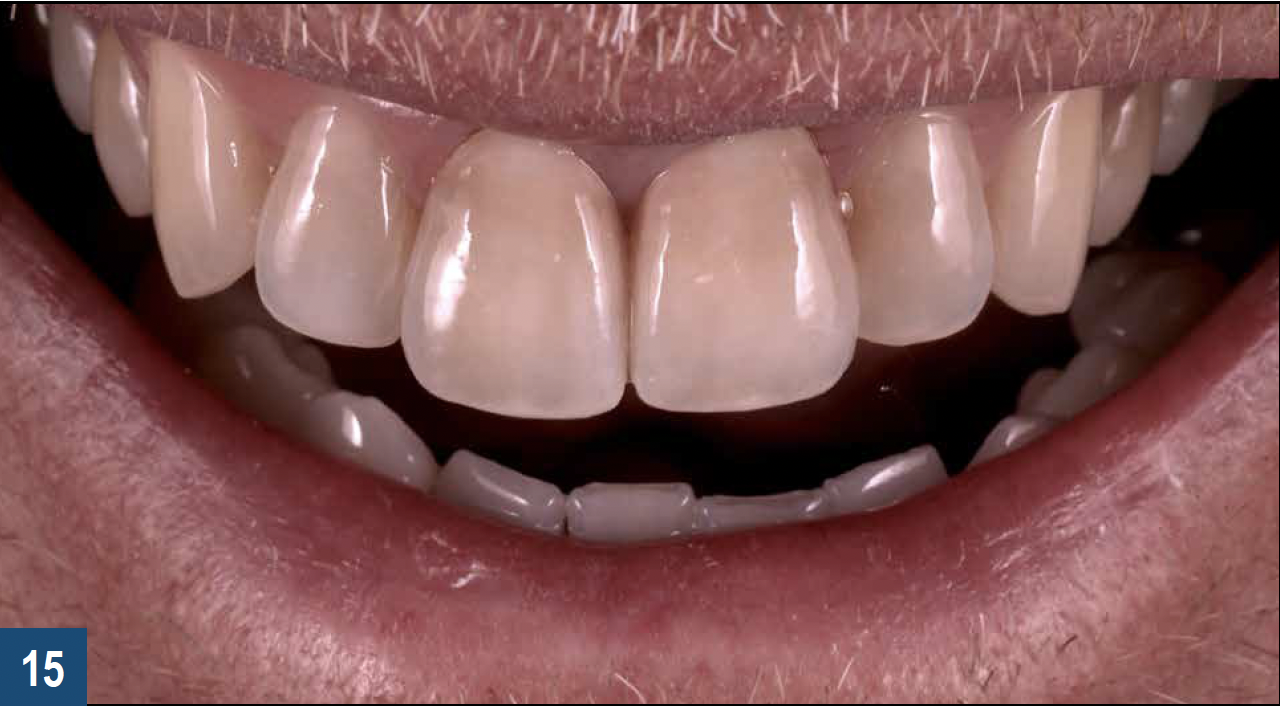

When a patient presents with previously restored nonvital anterior teeth (Figure 12), the challenge to produce a satisfactory esthetic outcome becomes a collaborative effort shared between the clinician and the dental labora-tory team. The darkened stumpf and subgingival root structure may produce an unfavorable shade to any definitive translucent ceramic restoration. In addition to its usefulness in intact nonvital teeth, the walking bleach technique with 10% carbamide peroxide is a safe and effective treatment modality for teeth with denuded enamel. Treatment to achieve the desired final shade may be completed within a single in-office application; however, the decision to discontinue internal bleaching will largely depend on the ceramist's abilities and knowledge of the materials being applied to mask the final stumpf shade of the tooth preparation (Figure 13 and Figure 14). Residual oxygen from the decomposition of 10% carbamide peroxide may remain within the dental tissues for 7 to 15 days after internal bleaching.39,40 This excess oxygen has the potential to negatively impact the bond strength of the adhesive components during the cementation of the final crowns, and it is therefore recommended that at least 2 weeks elapse before final delivery of the definitive restorations (Figure 15).41

Fig 15. Final delivery of full-contour porcelain crowns on the central incisors in the patient shown in Figure 14. For restorations that will be adhesively luted over internally bleached teeth, a minimum waiting period of 2 weeks should be observed to allow the dissipation of excess oxygen that may otherwise negatively impact the bond strength of the cement.

Figure 15